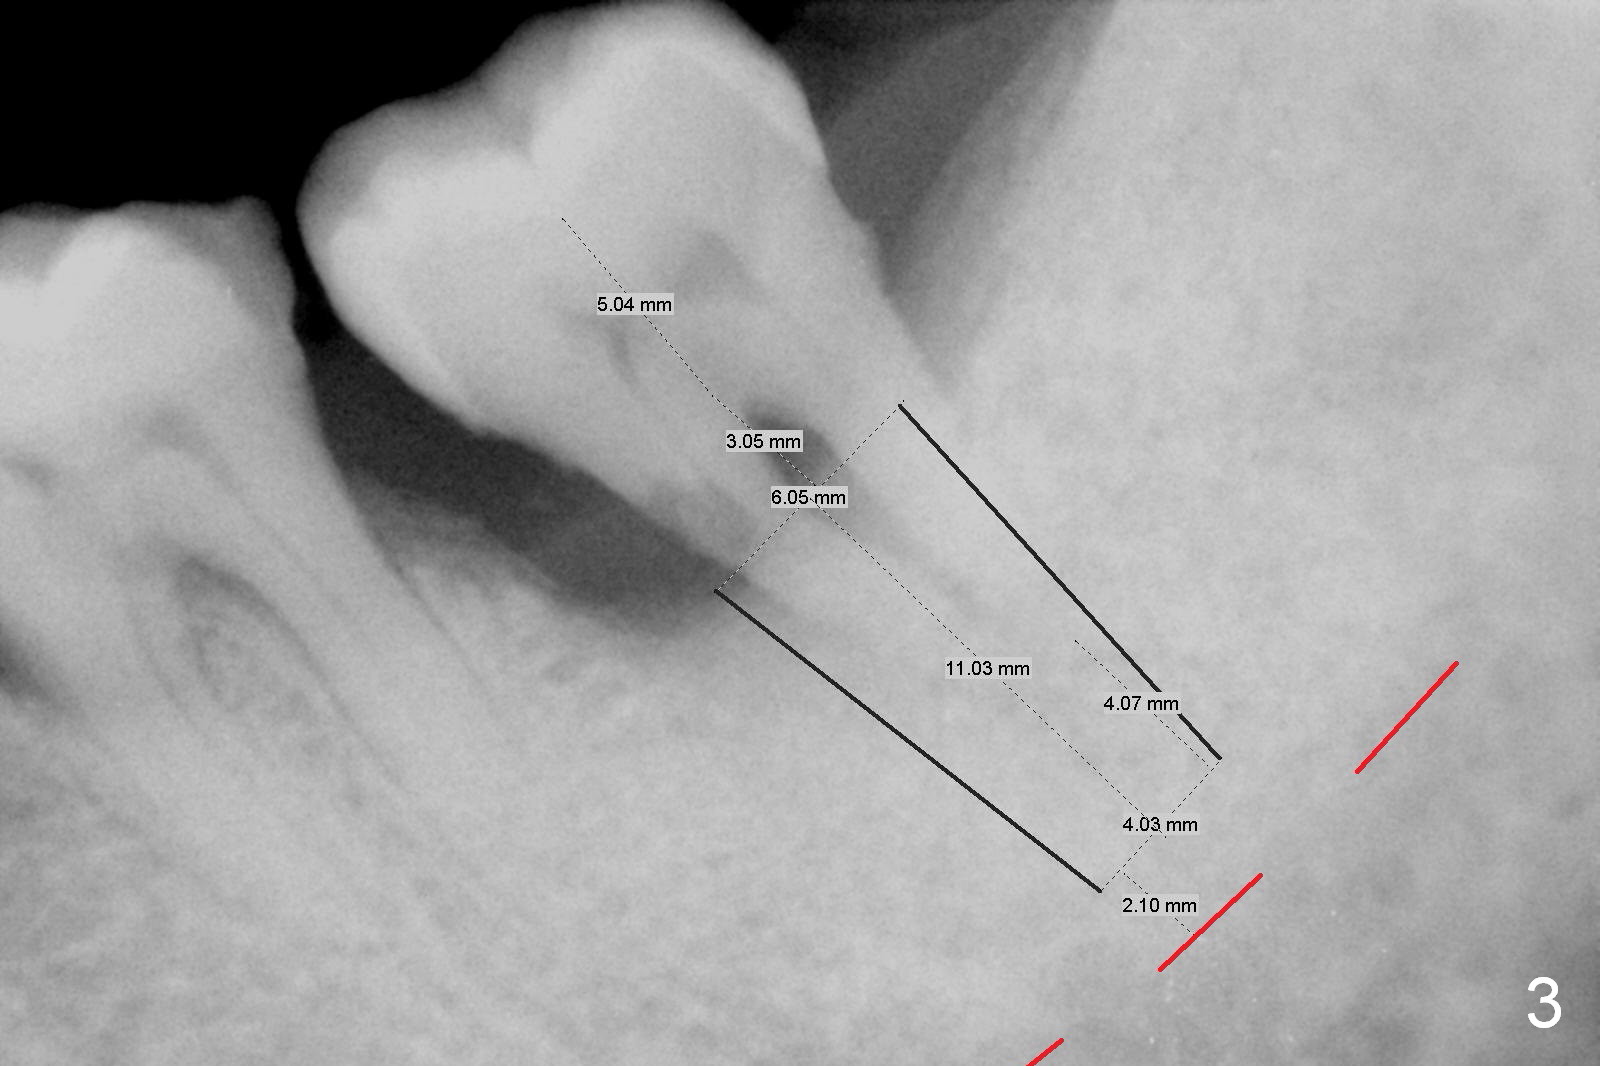

A 59-year-old man has history of chronic periodontitis (Fig.1 (taken in 2005), 2 (2014), 3 (2016)) involving the tooth #18. The bone loss may be complicated by bruxism. Large crown vs. narrow roots contributes to severe bone loss. An implant should be as long as possible and placed as coronally as possible to tackle crown/implant ratio issue. To prevent peri-implantitis, the implant may have to be placed deep. It appears that the bone height is more favorable mesially than distally (Fig.3). After extraction of the supraerupted and loose tooth (Fig.4; no Antibiotic), explore the socket to determine the favorite osteotomy site, most likely the mesial socket, lingually.